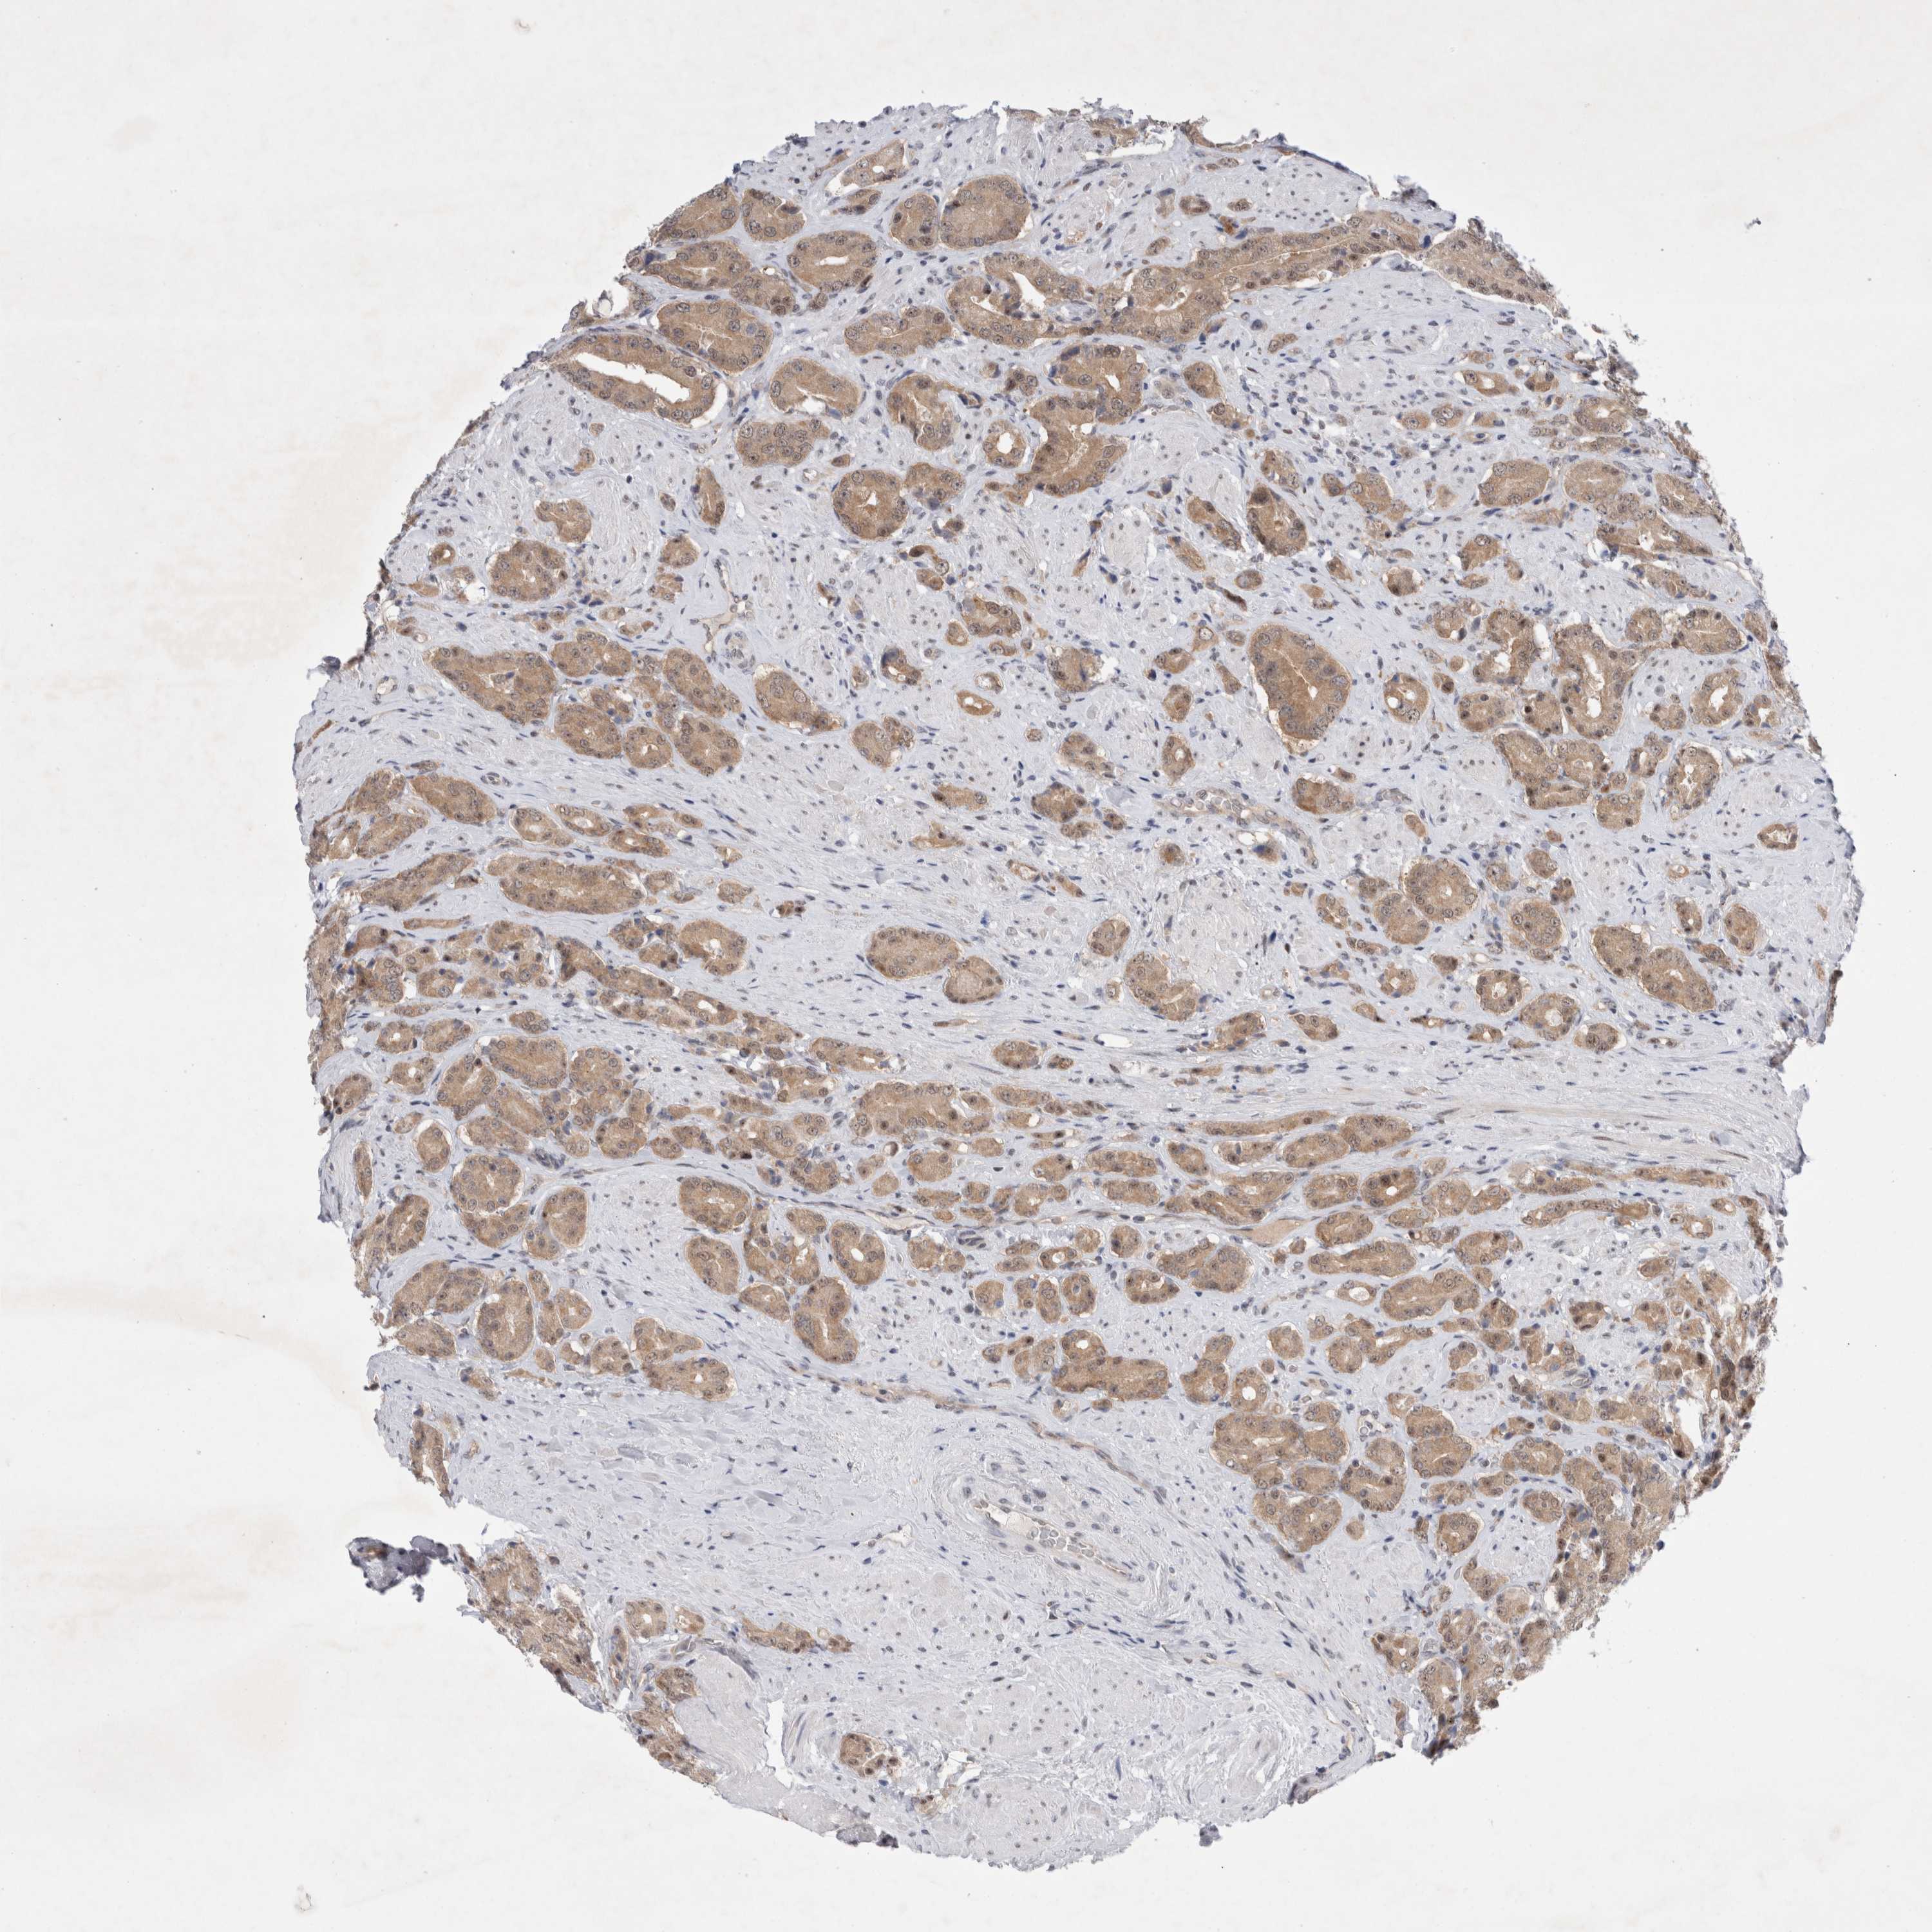

PROSTATE CANCER - Protein expressioni

A mouse-over function shows sample information and annotation data. Click on an image to view it in a full screen mode. Samples can be filtered based on level of antibody staining by selecting one or several of the following categories: high, medium, low and not detected. The assay and annotation is described here.

Note that samples used for immunohistochemistry by the Human Protein Atlas do not correspond to samples in the TCGA dataset.

Antibody stainingi

Antibody staining in the annotated cell types in the current human tissue is reported as not detected, low, medium, or high, based on conventional immunohistochemistry profiling in selected tissues. This score is based on the combination of the staining intensity and fraction of stained cells.

Each image is clickable and will lead to virtual microscopy that enables deeper exploration of all samples and also displays staining intensity scores, fraction scores and subcellular localization as well as patient and tissue information for each sample.

Antibody HPA024000

Antibody HPA024001

Antibody HPA024467

Staining

High

Medium

Low

Not detected

Intensity

Strong

Moderate

Weak

Negative

Quantity

>75%

75%-25%

<25%

None

Location

Nuclear

Cytoplasmic/membranous

Cytoplasmic/membranous,nuclear

Adenocarcinoma, High grade

Adenocarcinoma, Low grade